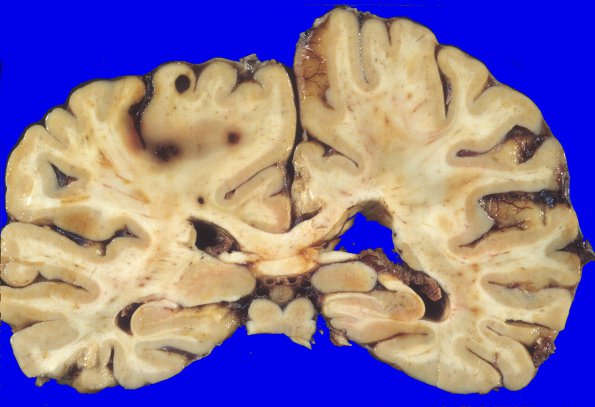

16A2 Metastasis, breast (Case 16) 3

Sections of the brain and cerebellum show metastatic carcinoma with extensive hemorrhage.